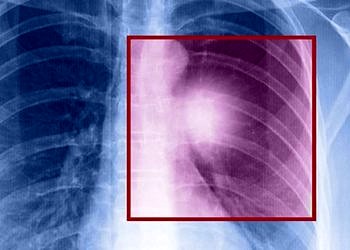

Akciğer naklinde başarı oranları artıyor

Türk Toraks Derneği Başkanı Prof. Dr. Ali Fuat Kalyoncu, kanserin, dünyada ve Türkiye'de sebebi bilinen ölümler arasında kalp ve damar...

Prof. Dr. Ali Fuat Kalyoncu, kanserin, dünyada ve Türkiye'de sebebi bilinen ölümler arasında kalp ve damar hastalıklarından sonra ikinci sırada...